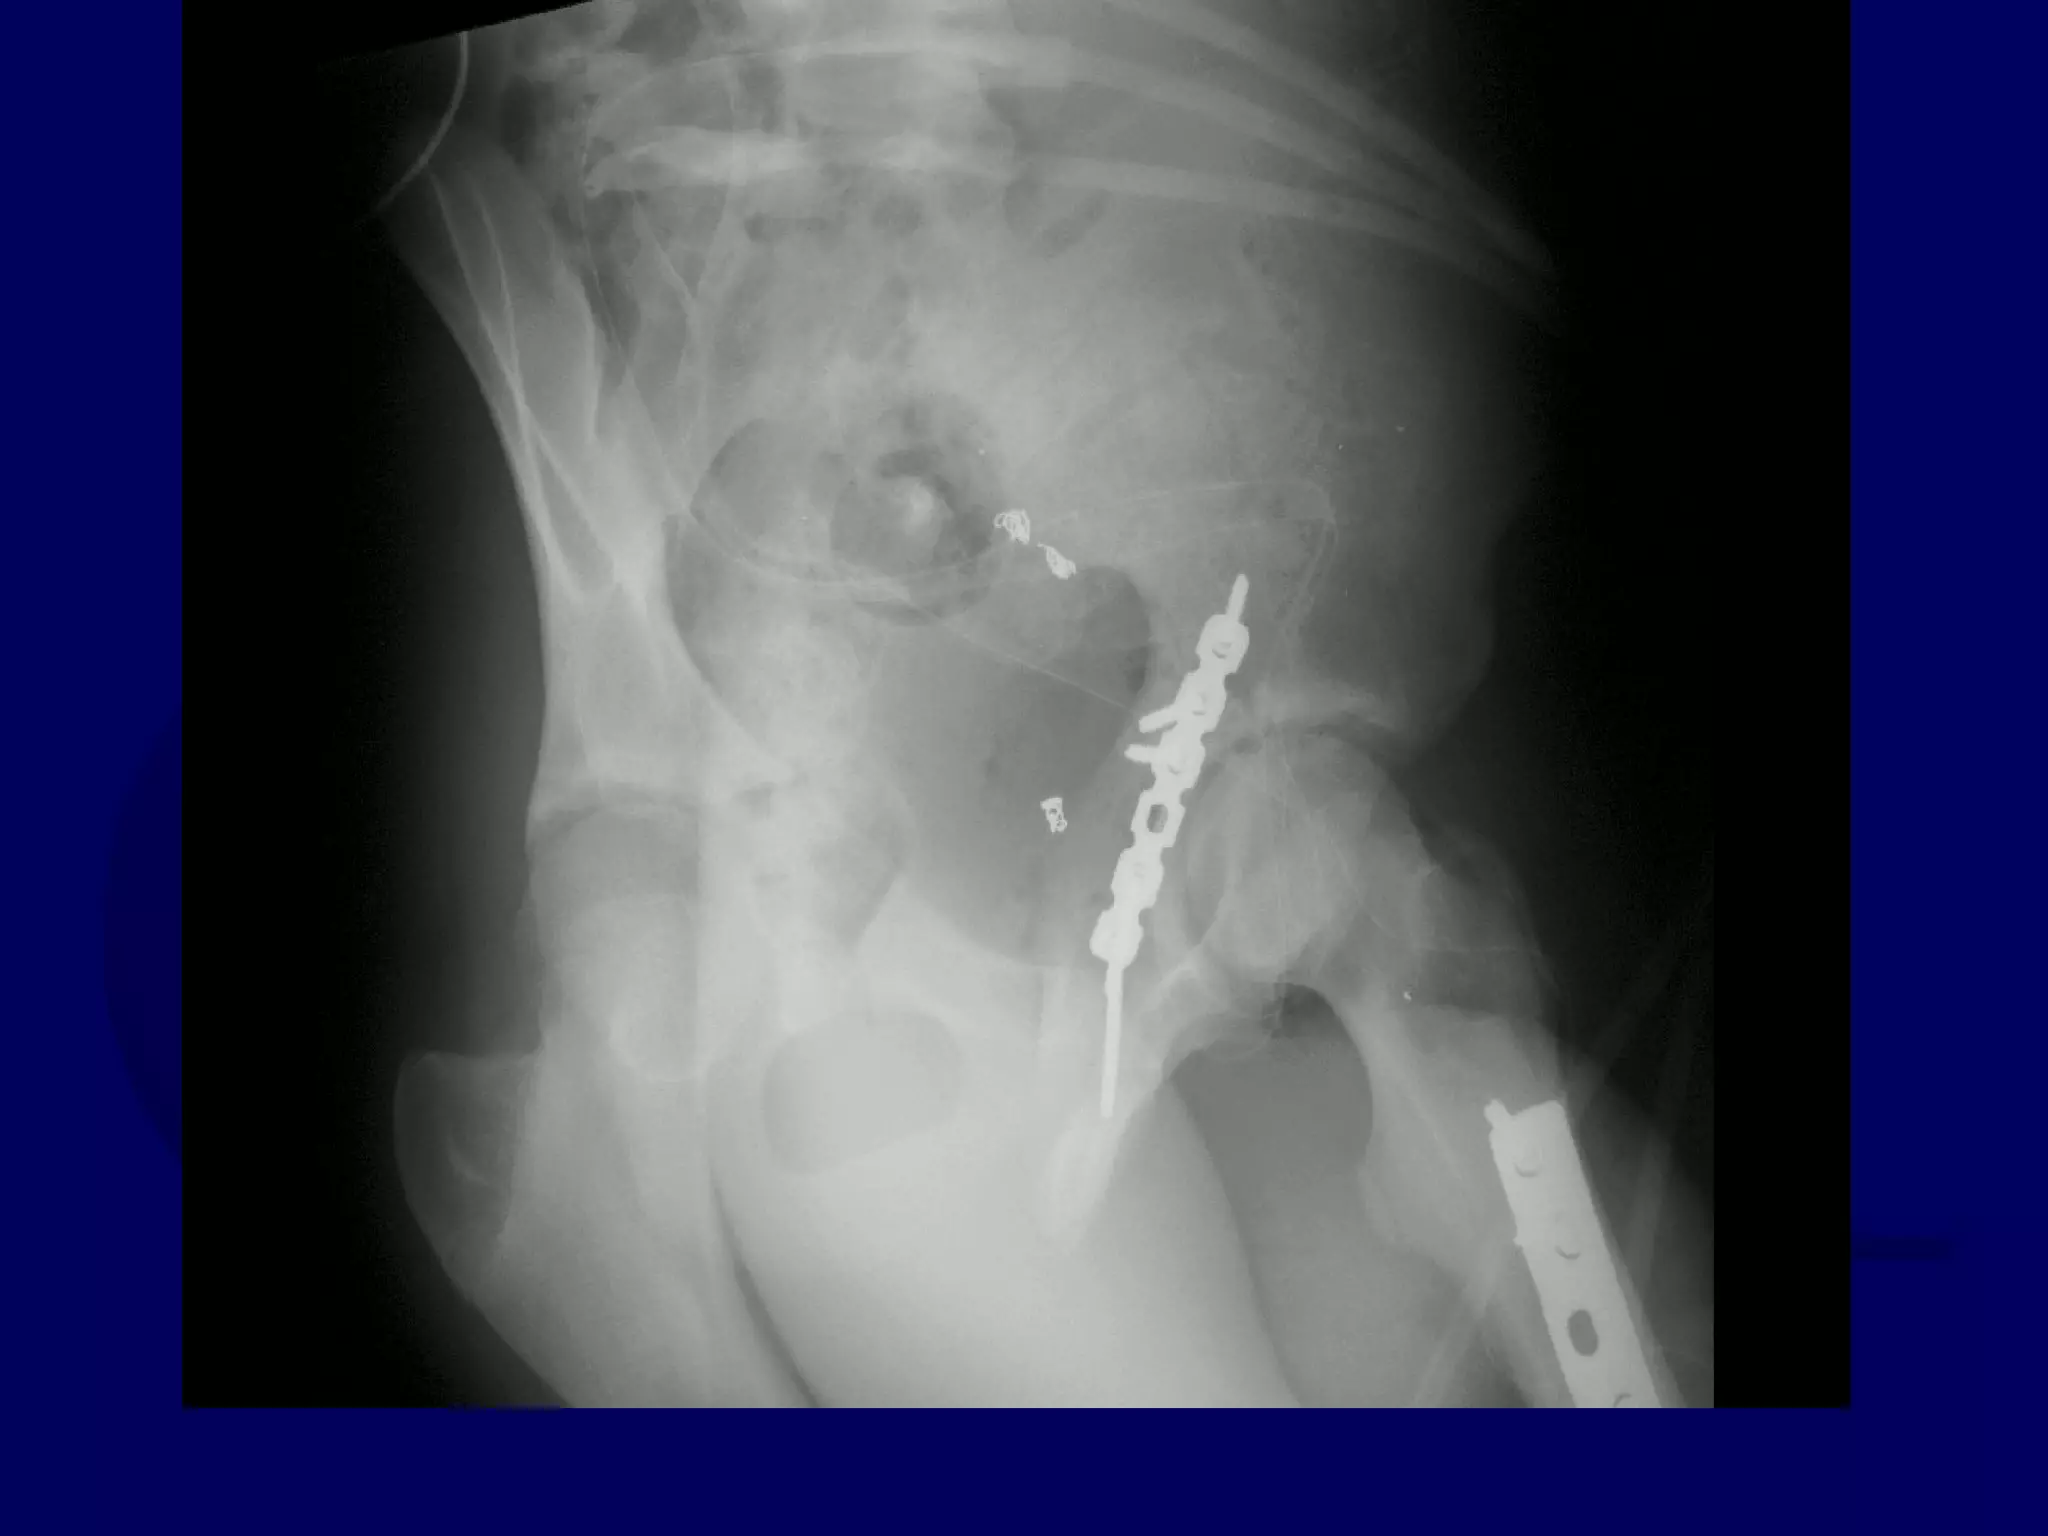

Both Column

Acetabular Fracture

18 Y.O. Female

Isolated Injury

Completion of Iliac Fracture

Reduction of Anterior Column

to Intact Ilium

Reduction of Posterior Column

INTACT ILIUM

R.C. 00.03.10